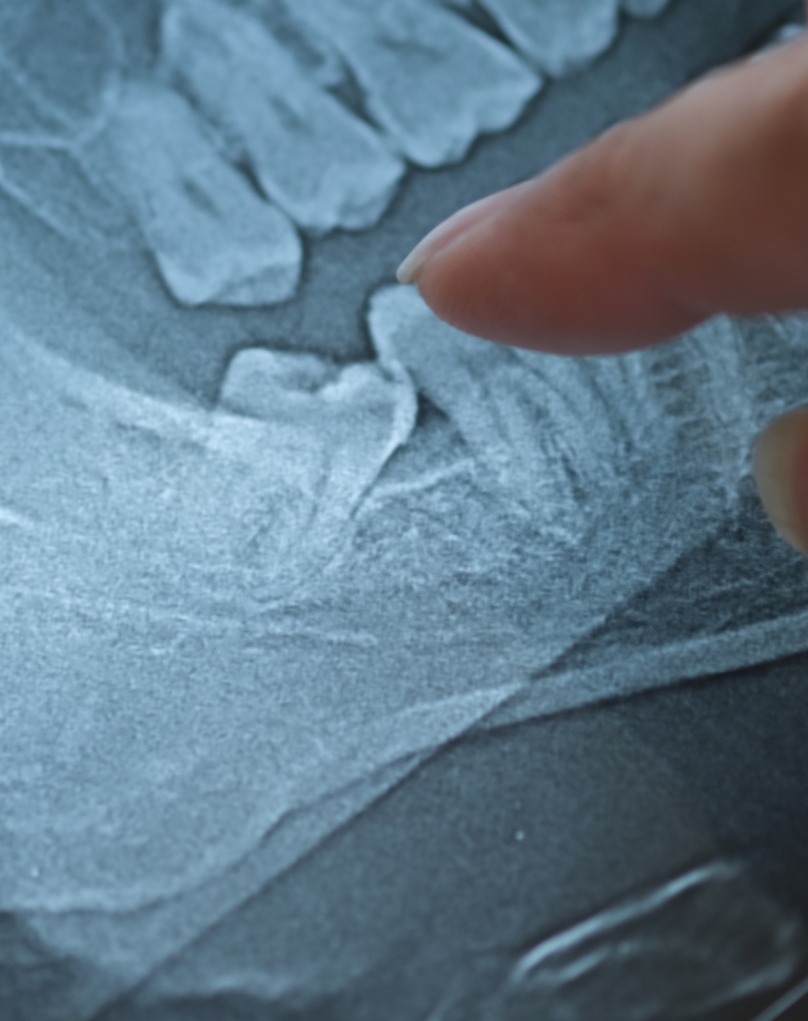

Extração dentária (simples ou complexa)

A extração dentária é indicada quando um dente está gravemente danificado, fraturado ou comprometido por cárie profunda.

• Extração simples: realizada quando o dente está visível e acessível, sem complicações.

• Extração complexa: indicada para dentes com raízes curvas, fraturados ou parcialmente cobertos pela gengiva.

Ambos os procedimentos são seguros e realizados sob anestesia local.